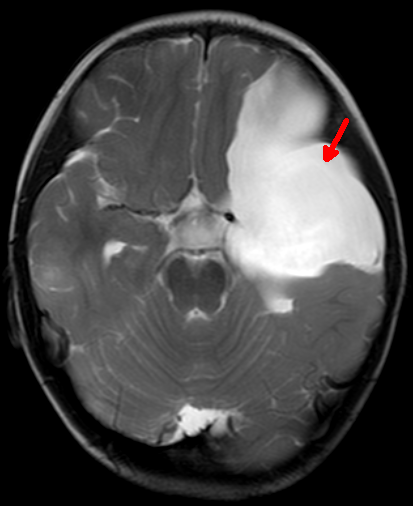

芳芳(化名)今年14岁,正值花季年龄的她却有着自己的烦恼。原来芳芳的生长发育跟同龄人相比明显迟缓,不但个头低于同龄人,并且有喝水多、上厕所频繁的现象,因此也变得不愿与人交流。家人不敢掉以轻心给女儿查了个头部的磁共振。不查不知道,这一查居然发现芳芳脑子正中间的位置有一个巨大“水球”,医学上叫做“鞍上池蛛网膜囊肿”,正是这个大水球压迫丘脑等重要结构引起了芳芳发育慢、尿崩等症状。当地医院条件有限,于是转入郑州大学五附院神经外科三病区就诊。付旭东主任带领其团队认真研究了患者的影像学资料,制定了神经内镜造瘘打开蛛网膜囊肿侧壁,把“死水”变成“活水”的手术方案。手术过程很顺利,术后喝水多、小便频繁的症状明显改善。由于神经内镜创伤很小,芳芳术后很快康复出院。

术前鞍上池巨大蛛网膜囊肿及其典型的“米老鼠”征